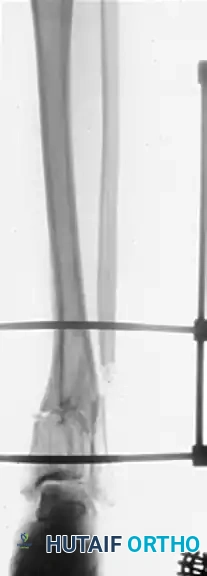

Preoperative AP and Lateral radiographs demonstrating a severe varus malunion of the distal tibia.

Intraoperative radiograph showing the osteotomy of the tibia and fibula, with the anatomical reduction maintained rigidly by a circular external fixator.